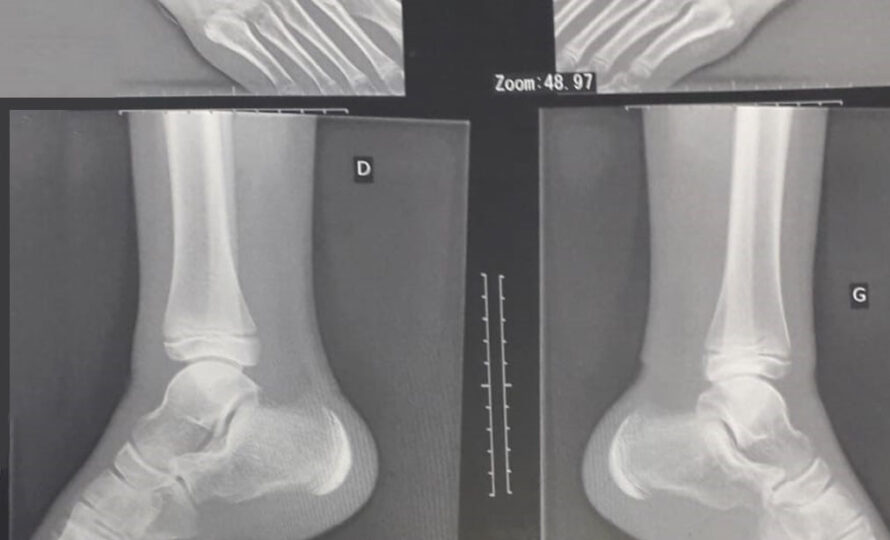

La Maladie de Sever

Aujourd’hui, découvrons la Maladie de Sever  Qu’est-ce que c’est ?Il s’agit d’une pathologie peu fréquente chez…